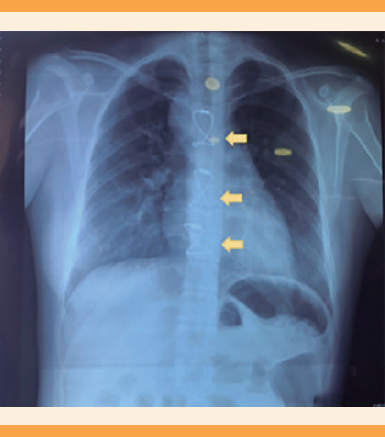

Paciente de 22 años, con diagnóstico a los 15 años de arteritis de Takayasu tipo V y tratamiento previo con prednisona (dosis no especificada). La paciente refirió haber recibido el diagnóstico de coartación de aorta, con aneurisma de la arteria mesentérica y una lesión en el plexo braquial por retención de un introductor en la arteria humeral; antecedente de colocación de un puente en la arteria mesentérica superior (2017), resección intestinal de 90 cm del íleo a 60 cm de la válvula ileocecal (2017), posoperada de un puente axilar humeral (2017) y derivación de la arteria aorta ascendente-aorta descendente (2018) (Figura 1). Tenía siete intervenciones quirúrgicas previas, sin acudir a seguimiento al servicio de Cardiología desde 2019. Ingresó al hospital a las 32.4 semanas de embarazo (con seis consultas de control prenatal en un centro de salud, pero sin referencia a un centro de tercer nivel de atención, ni valoración por un cardiólogo). En la revisión inicial se detectó la presión arterial en las extremidades superiores de 90-60 mmHg, segunda toma 100-70 mmHg, con leve disminución de los pulsos pedios. En la exploración física se encontró con modificaciones cervicales con las que se integró el diagnóstico de amenaza de parto pretérmino. Se le indió tratamiento tocolítico con 10 mg de nifedipino por vía oral cada 6 horas. Los exámenes de laboratorio al ingreso se reportaron normales. Durante la vigilancia, en la valoración por el reumatólogo se indicó enoxaparina en el puerperio. El cardiólogo propuso la finalización del embarazo. El ecocardiograma portátil reportó función preservada, sin datos de hipertensión pulmonar. La paciente fue valorada e ingresada a la unidad de cuidados intensivos. Durante la estancia permaneció sin remisión de la actividad uterina; se decidió finalizar el embarazo por vía abdominal, previa valoración por parte del intensivista, cirujano general y anestesiólogo para la colocación de un catéter venoso central, que se insertó por vía periférica guiado por ultrasonido (Figura 2). Se procedió a la cesárea, con anestesia general. Se obtuvo una recién nacida de 1970 g, talla de 41 cm, Apgar 7/8, Capurro de 34 semanas, Silverman Anderson 1. Placenta completa con sangrado de 250 cc. Durante la intervención se encontraron múltiples adherencias al intestino, íntima relación con la cavidad debido a las reintervenciones previas (Figura 3) pero sin complicaciones. La paciente se trasladó a la unidad de terapia intensiva, para observación, sin requerimiento de medidas de soporte avanzadas. La evolución fue favorable durante cuatro días, más otro en el piso de ginecología y obstetricia, con posterior alta del hospital.